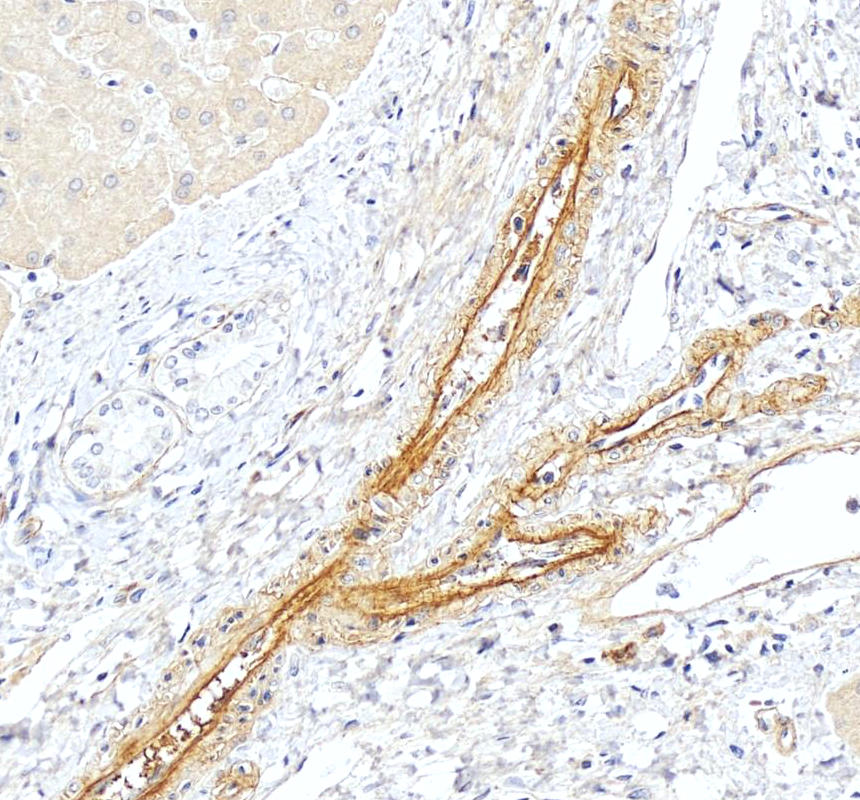

IHC analysis of HSPG2 using anti-HSPG2 antibody (PB9277).

HSPG2 was detected in a paraffin-embedded section of human lung cancer tissue. Biotinylated goat anti-rabbit IgG was used as secondary antibody. The tissue section was incubated with rabbit anti-HSPG2 Antibody (PB9277) at a dilution of 1:200 and developed using Strepavidin-Biotin-Complex (SABC) (Catalog # SA1022) with DAB (Catalog # AR1027) as the chromogen.